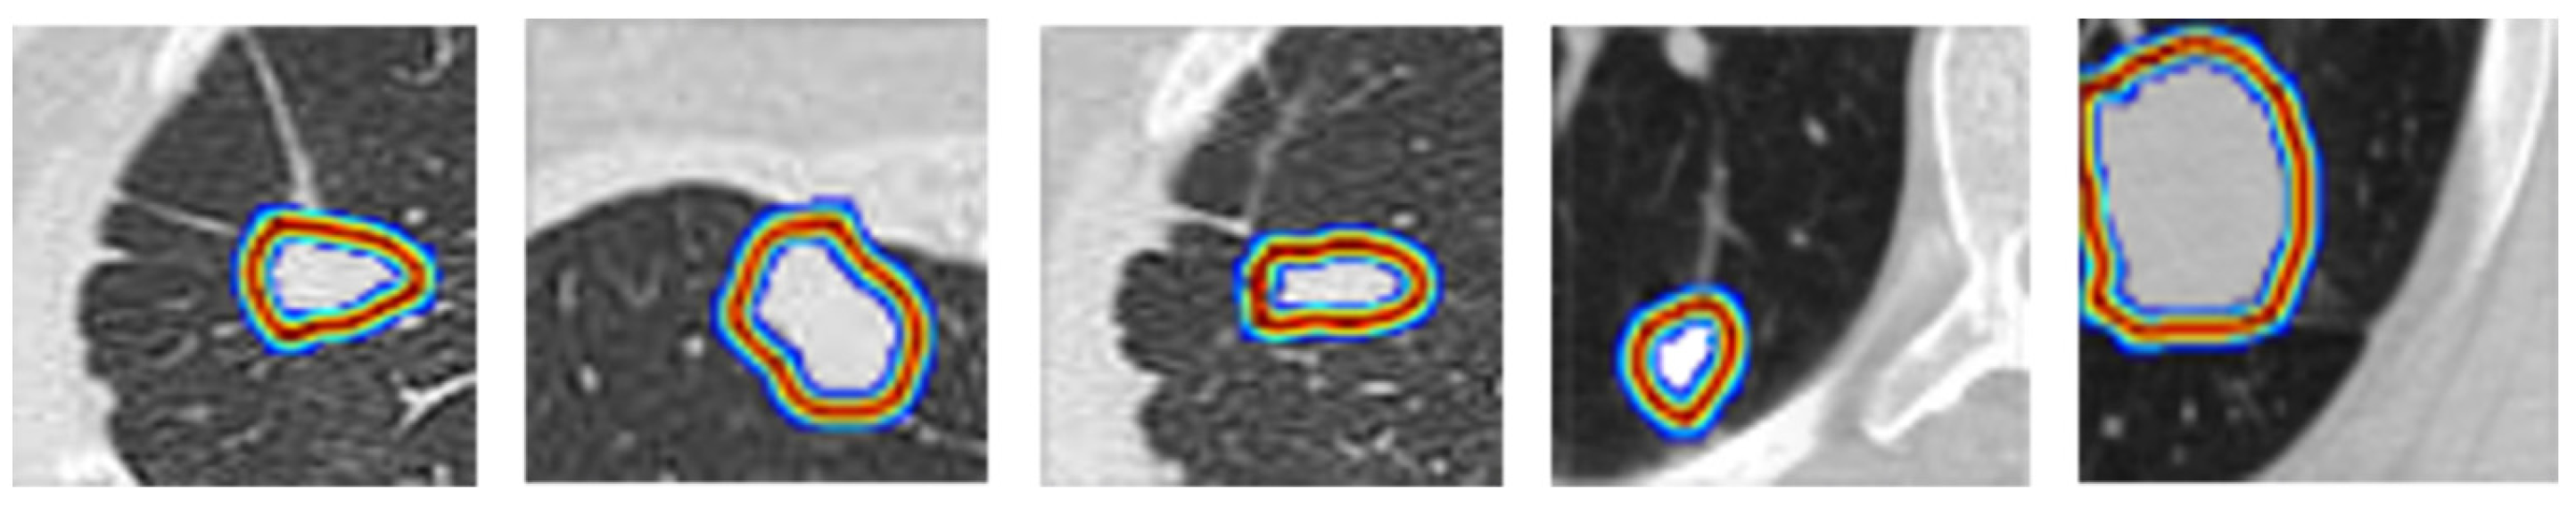

5.3. Qualitative Analysis